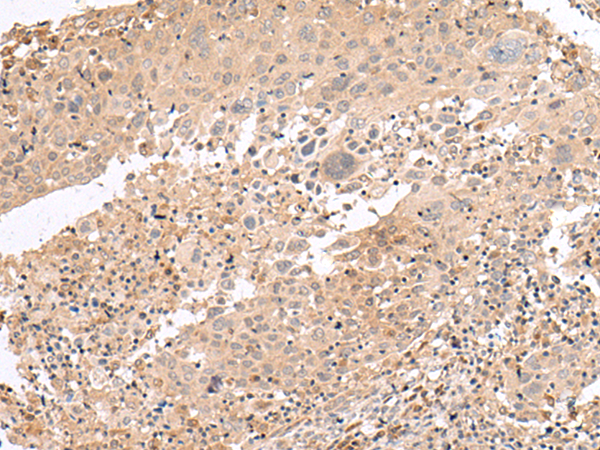

IHC positive control: |

Human cervical cancer |

IHC Recommend dilution: |

40-200 |